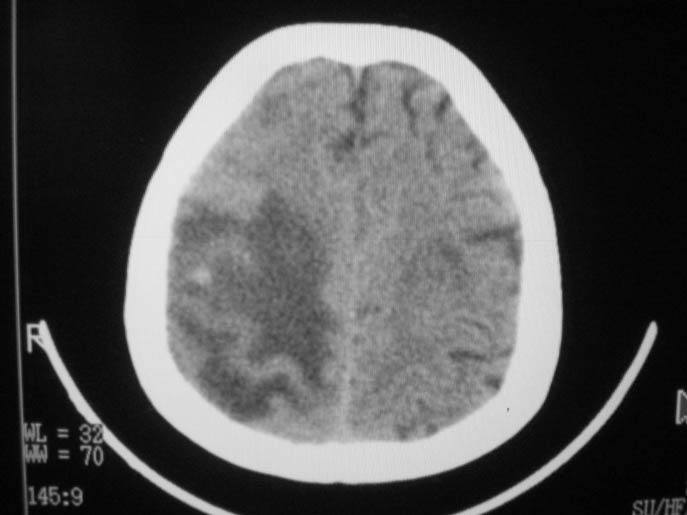

以下是引用卜一在2009-9-7 16:23:00的发言:[br]支持:胶质瘤伴出血!

以下是引用随光逐影在2009-9-8 7:40:00的发言:[br]考虑脑转移瘤或胶质瘤并肿瘤卒中;建议行ct增强扫描检查。

以下是引用熊熊在2009-9-7 18:31:00的发言:[br]胶质瘤伴出血[br]建议增强